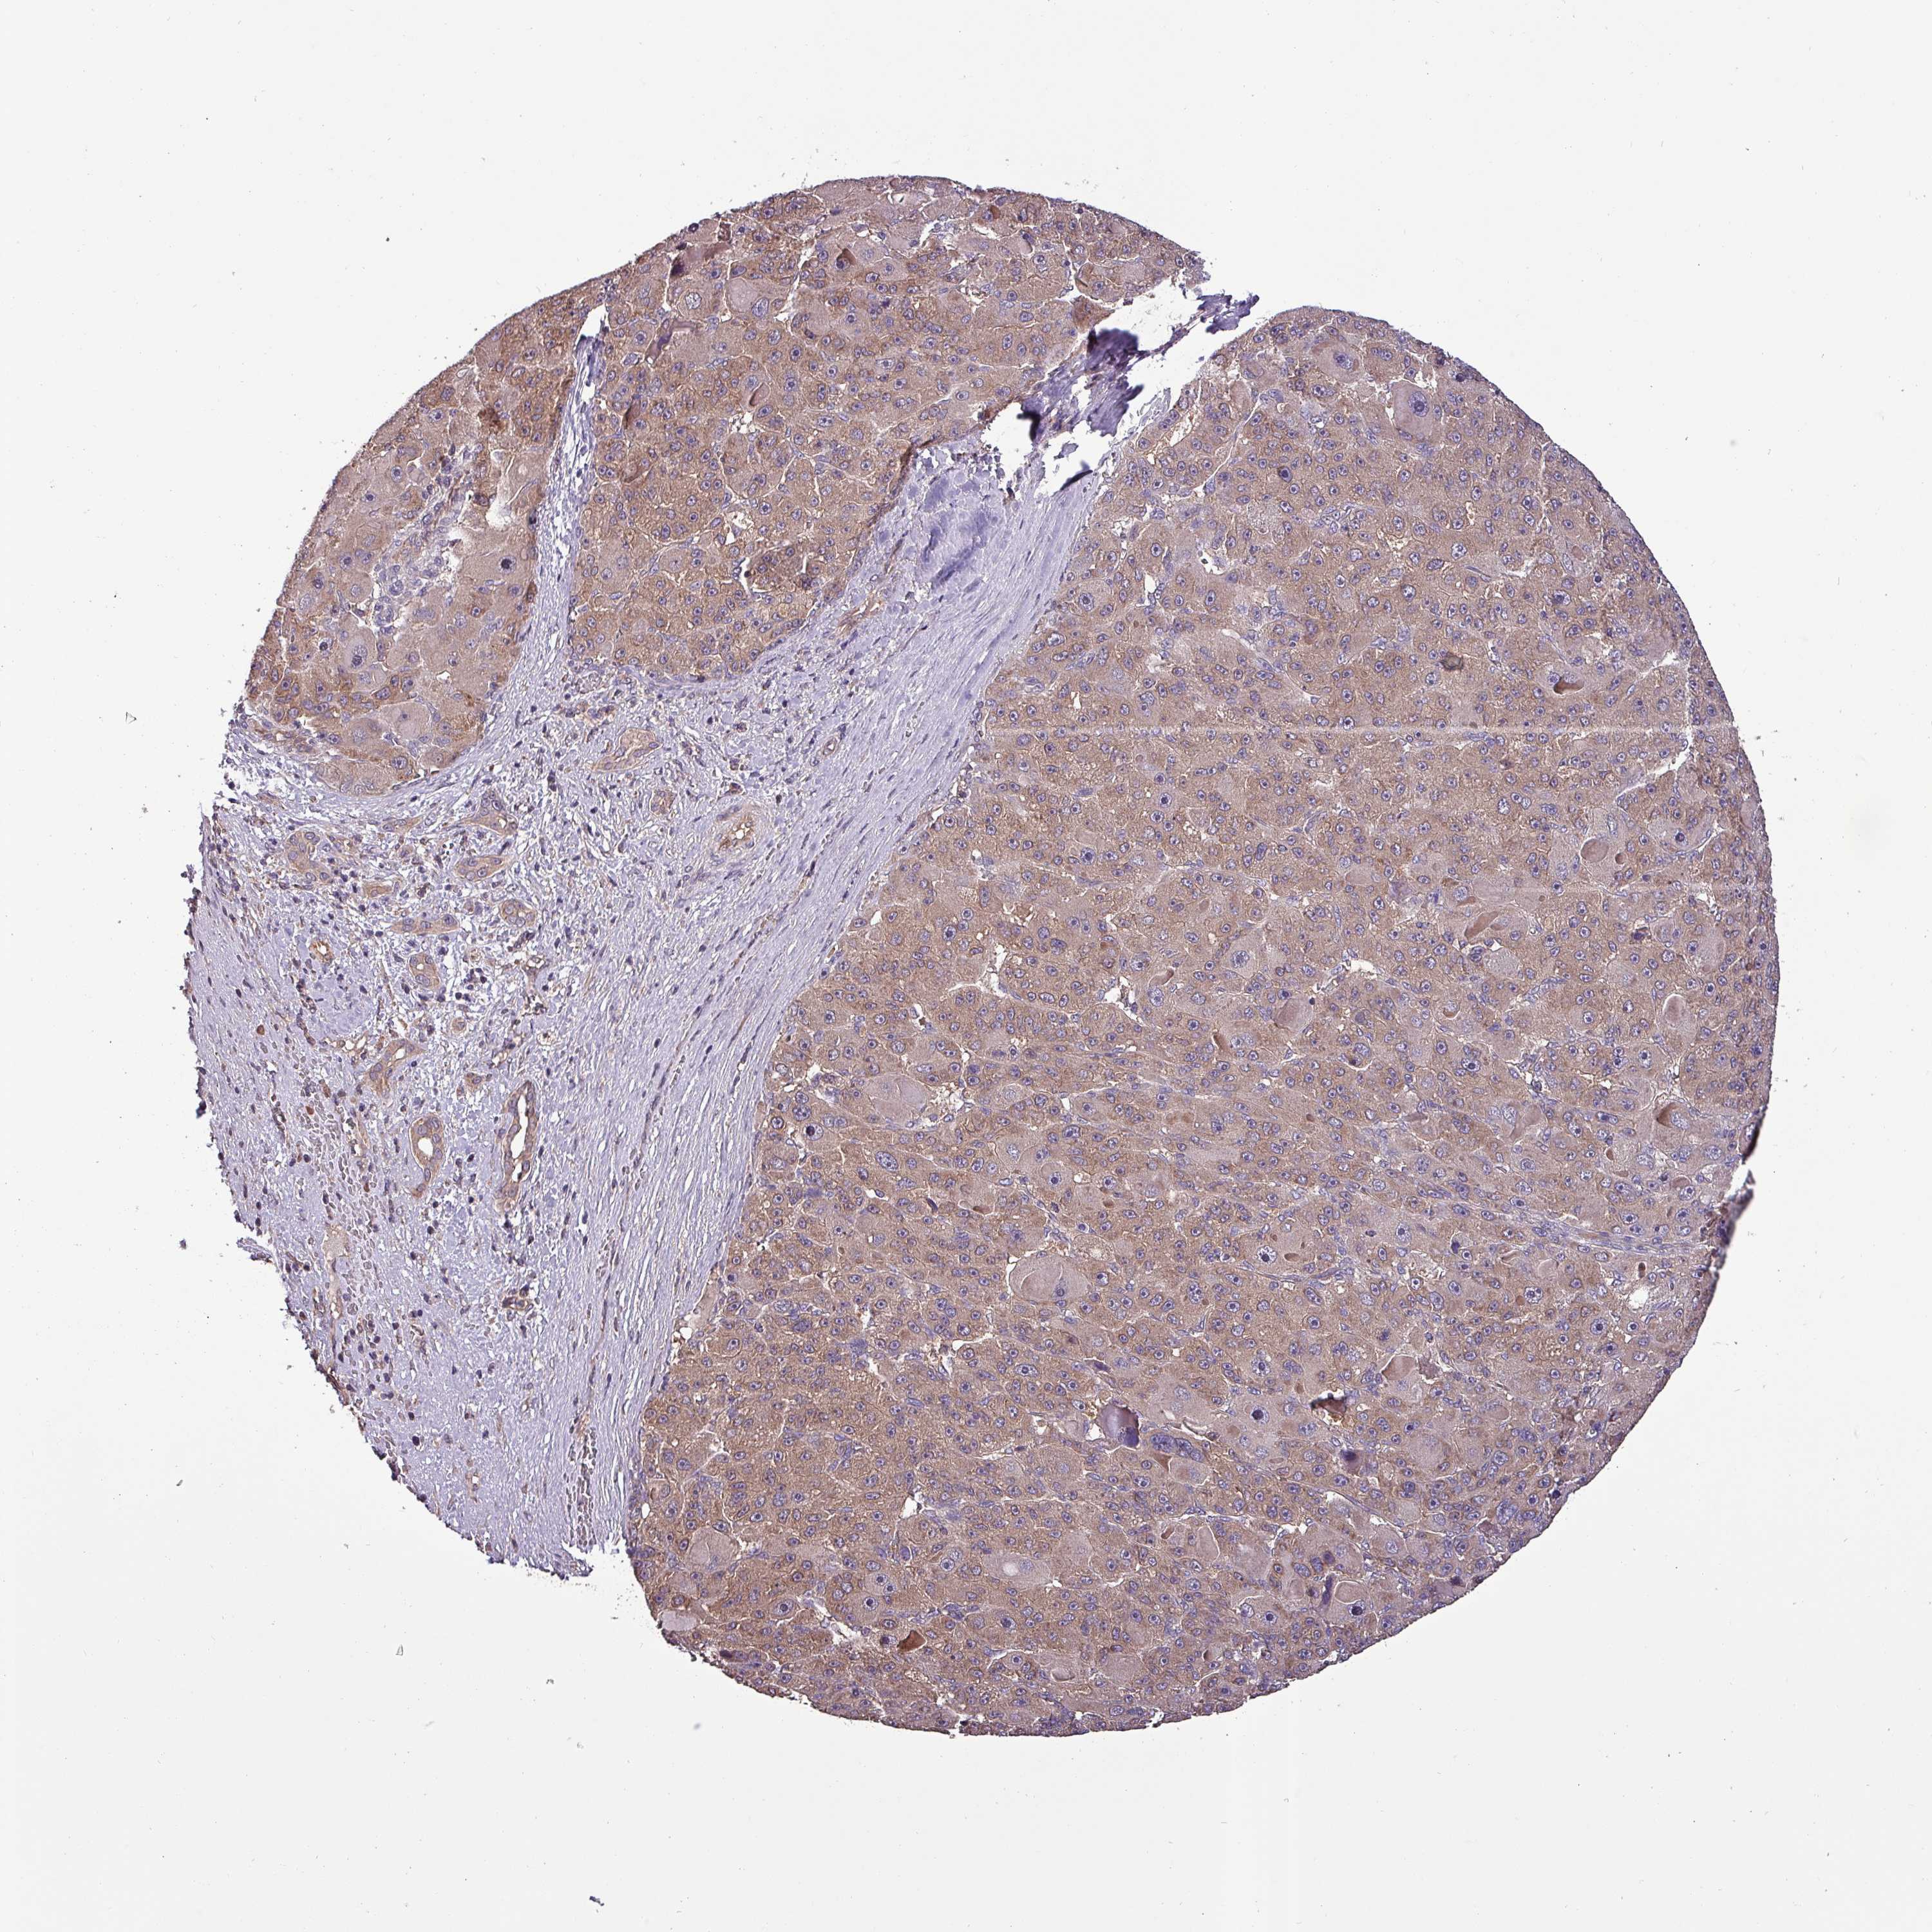

LIVER CANCER - Protein expressioni

A mouse-over function shows sample information and annotation data. Click on an image to view it in a full screen mode. Samples can be filtered based on level of antibody staining by selecting one or several of the following categories: high, medium, low and not detected. The assay and annotation is described here.

Note that samples used for immunohistochemistry by the Human Protein Atlas do not correspond to samples in the TCGA dataset.

Antibody stainingi

Antibody staining in the annotated cell types in the current human tissue is reported as not detected, low, medium, or high, based on conventional immunohistochemistry profiling in selected tissues. This score is based on the combination of the staining intensity and fraction of stained cells.

Each image is clickable and will lead to virtual microscopy that enables deeper exploration of all samples and also displays staining intensity scores, fraction scores and subcellular localization as well as patient and tissue information for each sample.

Antibody HPA051836

Staining

High

Medium

Low

Not detected

Intensity

Strong

Moderate

Weak

Negative

Quantity

>75%

75%-25%

<25%

None

Location

Nuclear

Cytoplasmic/membranous

Cytoplasmic/membranous,nuclear

Carcinoma, Hepatocellular, NOS